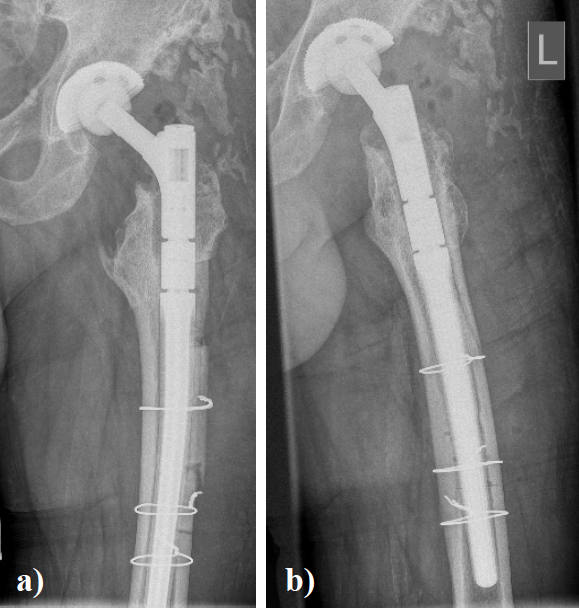

In August 2013 THA was performed due to a girdlestone situation after septic osteoarthritis of the hip (Figure 1) in a 46 year old male patient using a MRP Titan revision stem (Diameter: 18mm, length: 140 mm) (Peter Brehm GmbH, Weisendorf, Germany) and a cementless cup (Allofit - IT; Diameter 54 mm, Zimmer, Warsaw, USA) and a ceramic on ceramic bearing (head diameter: 36 mm) (Figure 2). The patient was 175 cm tall and weighed 105 kg (body mass index: 34.3 Kg/ m2). 2 weeks later revision surgery due to recurrent dislocation (Figure 3) was performed. Revision of the acetabular component was done using an Allofit - Classic- cup, Diameter 56 mm (Zimmer, Warsaw, USA)). The neck component was exchanged from small to medium size (Figure 4). A ceramic on PE bearing was implanted (head diameter: 32 mm). Postoperative healing was uneventful. The patient was out of any complaints. In February 2016 the patient started suffering from slight thigh pain but detected crepitation in the region of the left hip. X-ray of the left hip in 2 planes in May 2016 revealed an asymmetrically gap of the stem / neck junction (Figure 5). During revision surgery of the left hip breakage of the cone of the morse taper junction was visible (Figure 6). Removal of the well-fixed stem was performed via a distal fenestration. After fixation with cerclage wires a bended MRP Titan revision stem (Diameter: 19 mm, Length: 200mm with long neck and extension sleeve) was implanted using a 32 mm ceramic head (Figure 7). Postoperative healing was uneventful.

Figure 4. X - ray of the left hip in 2 planes: ap view a. and lateral; b view shows status after revision of THA using a long varus neck and a cementless cup.